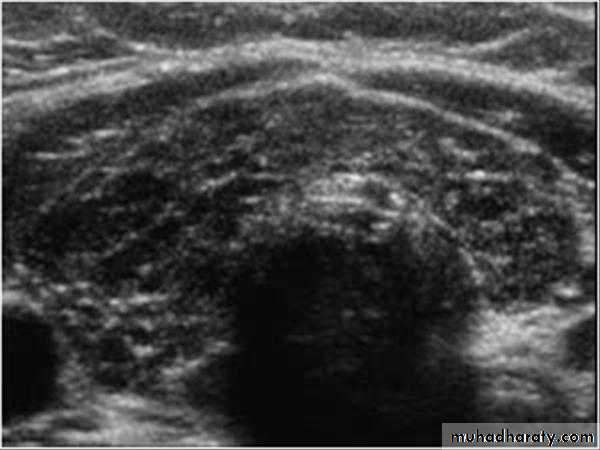

• US is the imaging investigation of choice for characterization of thyroid nodules.

• Features of thyroid nodules assessed with US include:• Size: the incidence of cancer in nodules smaller than 1 cm is extremely low

• Composition: cystic, solid or mixed

• Margins: well-defined margin or ‘halo’; irregular margins

• Calcification: coarse or fine

• Vascularity.